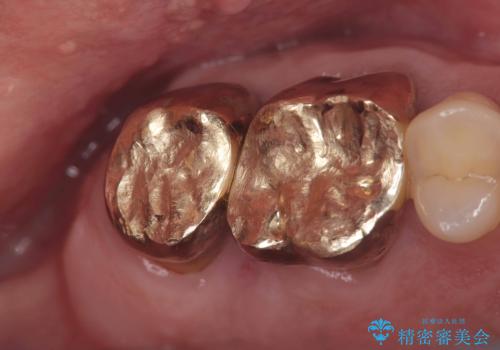

- 治療計画

- 当院にて根管治療を行いましたが、病変の改善が得られなかったため、インプラント治療を行う方針といたしました。

抜歯即時埋入の適応と判断し、抜歯当日にインプラント埋入を行う「抜歯即時埋入」にて処置を実施しました。